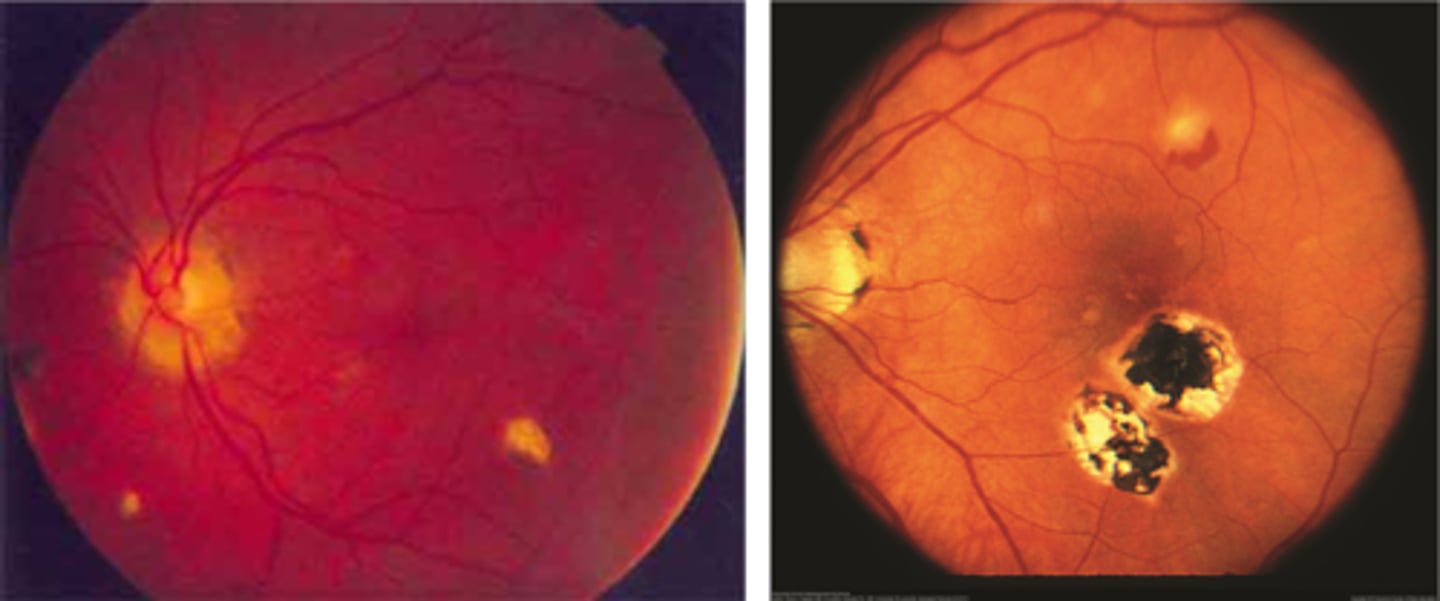

What findings of degenerative myopia are seen here?

PPA

crescent

lacquer cracks

What are lacquer cracks and what causes them?

breaks in Bruch's membrane that can expand and contract, mostly seen in degenerative myopia

How do lacquer cracks appear on fundoscopy?

jagged, irregular yellow lines showing sclera in the posterior pole

What is the main complication of lacquer cracks?

CNV in 29% of pt's